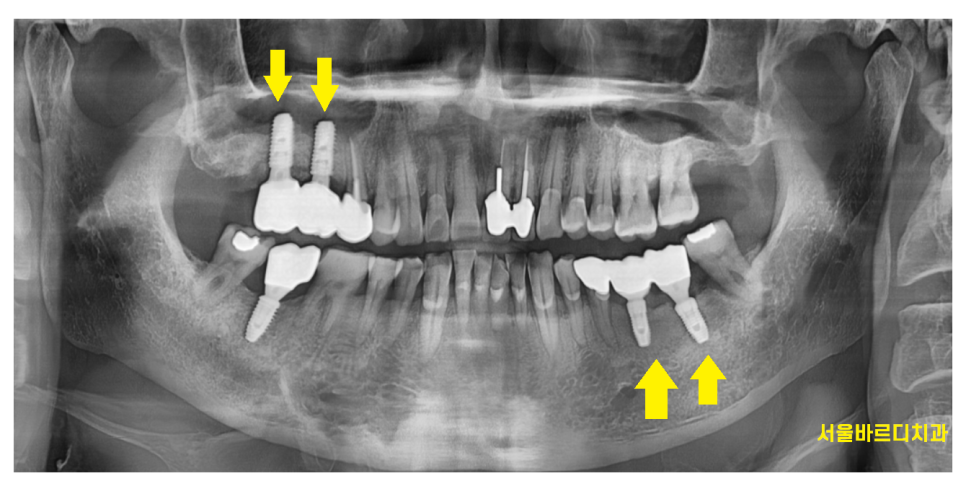

임플란트는 브릿지 형태로 치료를 많이합니다.

이 형태가 2가지인데

1)치아 갯수가 부족하여 브릿지로 연결하는경우

- 개수는 맞지만 임플란트끼리 엮는 경우

오늘 설명드릴 내용은 2번입니다.

24.01.23

위에 사진속 환자분처럼

치아가 상실된 개수가 1개도 없지만

임플란트는 묶어서 제작해드렸습니다.

임플란트는 각각 심었는데 말이죠~?